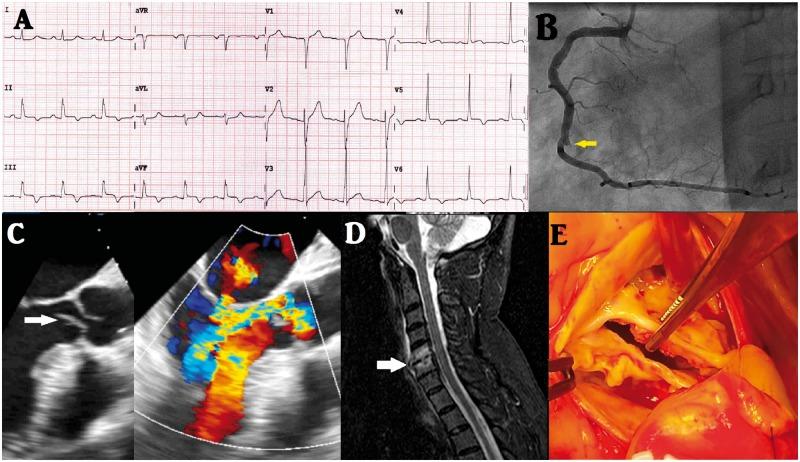

感染性心内膜炎相关心肌梗死:病例系列

Myocardial infarction associated with infective endocarditis: a case series.

CASE PRESENTATION

We report a case series of three patients with acute coronary syndrome (ACS) in IE. The first patient presented with non-ST-elevation ACS. He underwent a stent placement for late-diagnosed embolic myocardial infarction, after which he was treated conservatively without valve replacement, with good results. The second patient with ST-elevation presented with ACS, for which conventional balloon angioplasty and successful double valve replacement were performed. ST-elevation ACS was also observed in the last patient, who experienced periannular complications, which necessitated surgery.

病例介绍

我们报告了一组3例感染性心内膜炎合并急性冠状动脉综合征(ACS)的病例。首例患者表现为非ST段抬高型急性冠状动脉综合征。他因延迟诊断的栓塞性心肌梗死接受了支架置入术,之后接受保守治疗,未进行瓣膜置换,效果良好。第二例ST段抬高型患者表现为急性冠状动脉综合征,为此进行了传统球囊血管成形术并成功进行了双瓣膜置换。最后一例患者也出现了ST段抬高型急性冠状动脉综合征,伴有瓣周并发症,需要进行手术。